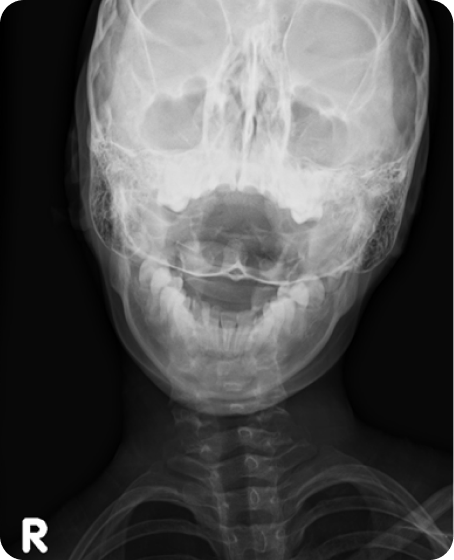

▲ CTA 5개월 착용 (2016년 6월 29일)